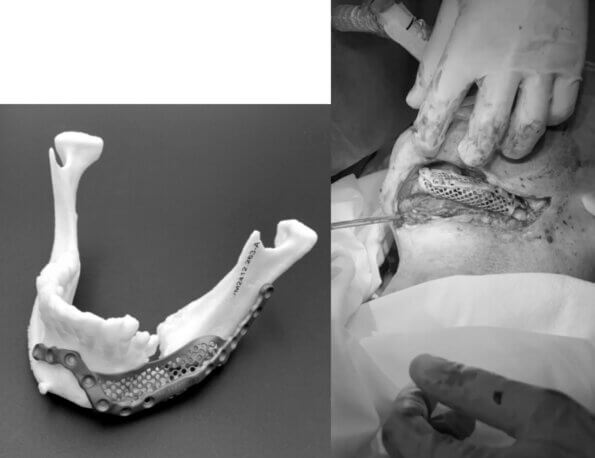

- Also in Zaporizhzhia, a soldier with a shattered lower jaw underwent surgery. Thanks to a custom-made titanium implant, his jaw was restored.